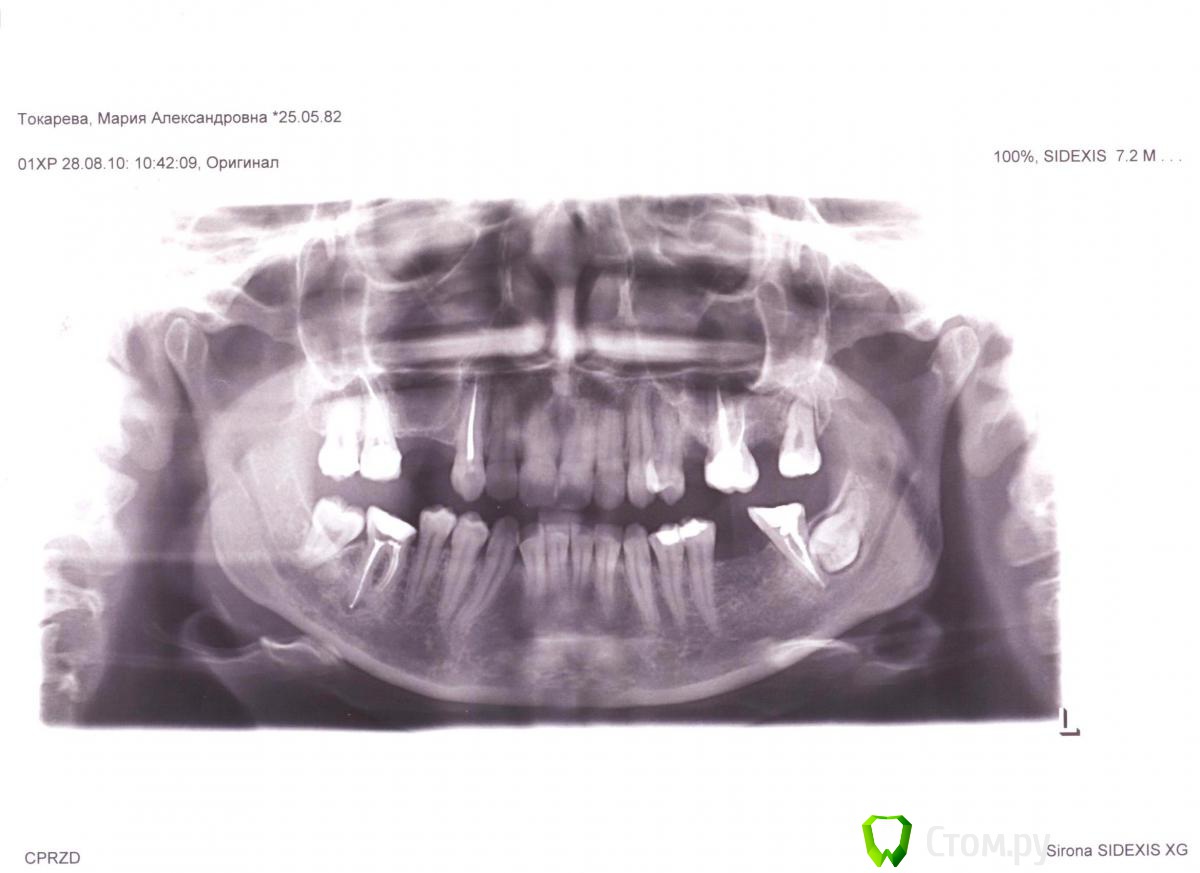

2,5 года прохожу ортодонтическое лечение на брекетах  системы Виктори ( металлических)., в последствии буду протезироваться на имплантах

Прилагаю все имеющиеся снимки ( до и сейчас) и фото данный момент.

1-в общем, есть вопросы по каналам депульпированных зубов

2-смущает окклюзионная плоскость на нижней челюсти.

3- 37-зуб возможно стоит "выпрямить более вертикально))"

4-Так же стоит обратить внимание на изменения в суставе, возможно стоит дообследоваться, опять же, по ОПТГ об этом не судят, но изменения есть, скорее всего это связано с отсутствием моляров. Проблемы с ассиметричным положением нижней челюсти решаться, с исправлением окклюзионнй плоскости, и восстановлением межальвеолярной высоты.

5-38 зуб- я бы рекомендовал убрать)